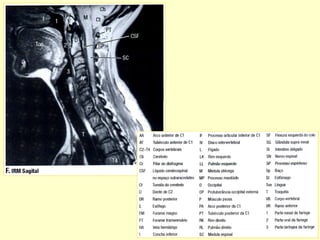

PADRÃO ‘ OURO’ PARA AVALIAR A

COLUNA POR MÉTODO DE IMAGEM

É A RESSONÂNCIA MAGNÉTICA.

Conteúdos intra-raquianos

RELAÇÕES ANATÔMICAS DA COLUNA

ANATOMIA RADIOLÓGICA CERVICAL

Anatomia radiológica